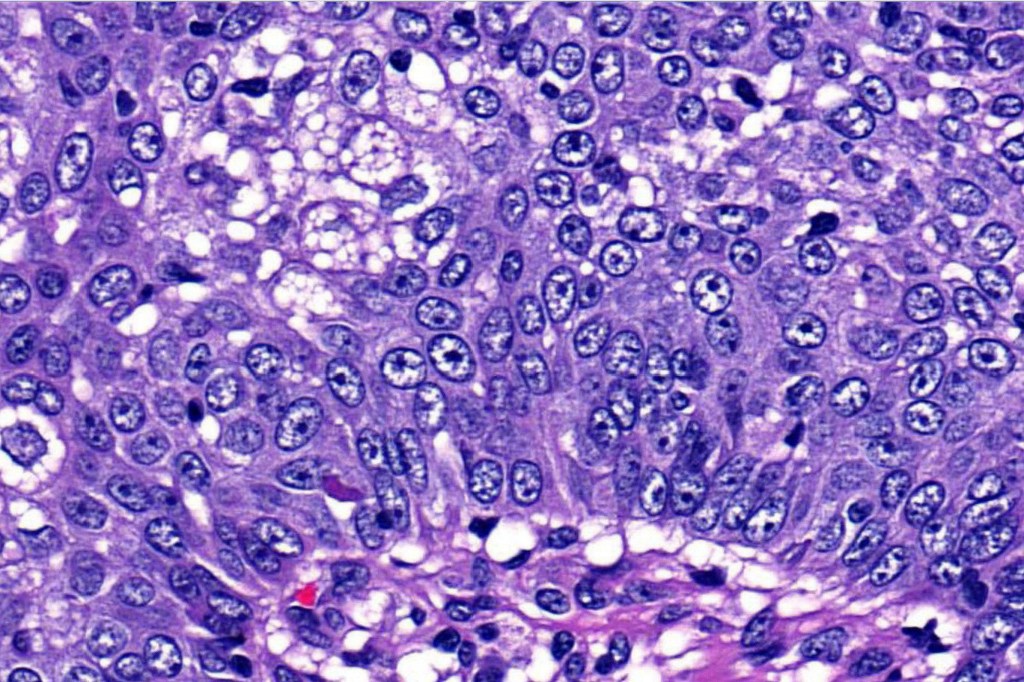

•Well differentiated lobular growth pattern though to a poorly differentiated tumor often showing a diffuse, infiltrating border which may extend into the subcutaneous fat

•Tumors are composed of an admixture of darkly staining basaloid cells with hyperchromatic or vesicular nuclei and more obvious sebaceous cells with eosinophilic, bubbly, multivacuolated cytoplasm frequently indenting the nucleus (scalloped)

•Often mitoses are numerous and abnormal forms evident

Sebaceous carcinoma from a patient with Muir-Torre syndrome kindly shared by Dr. Antonina Kalmykova.